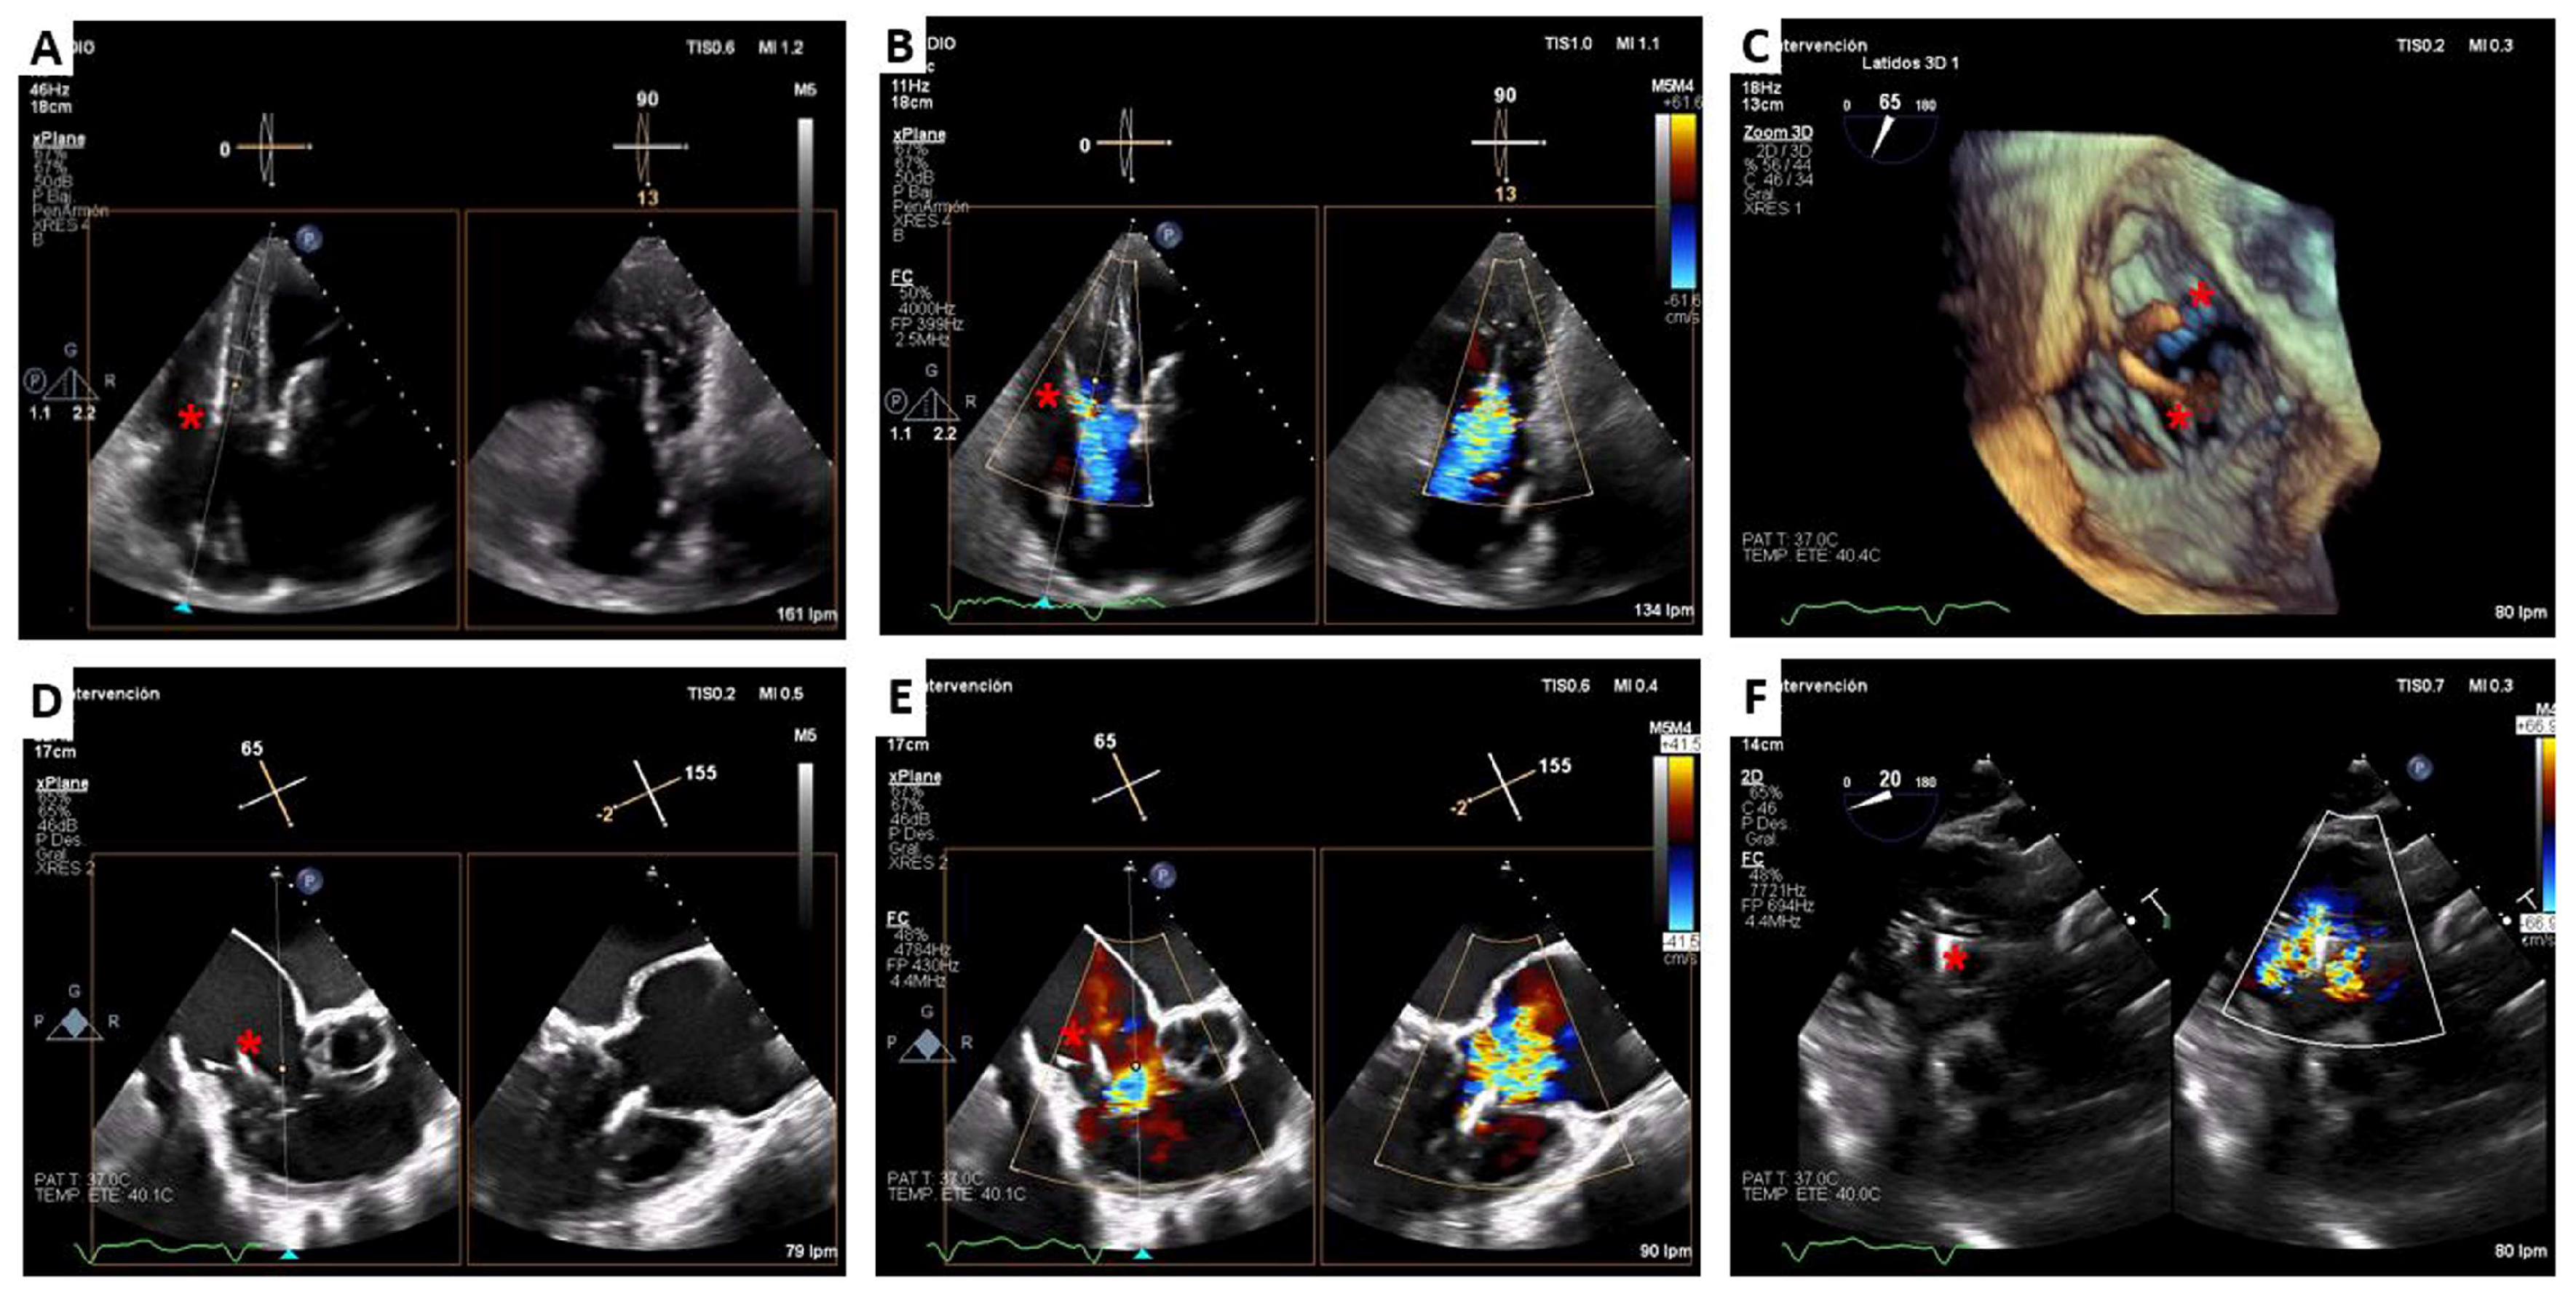

3. Lux-Valve Plus Case

4.4. LuX-Valve